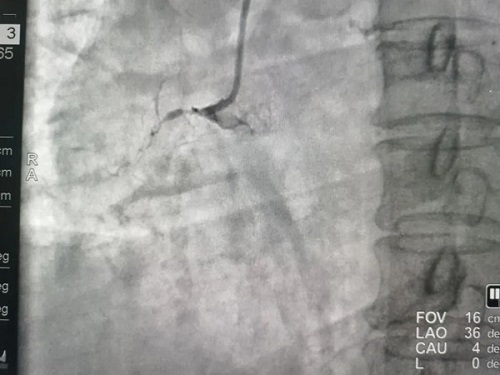

患者龙某,女,59岁,因胸痛2天加重2小时入院,2024年3月9日冠状动脉造影示左主干正常,前降支近中段长斑块,狭窄90%,TIMI血流3级,可见逆向血流至右冠远端;高位钝缘支可见散在斑块,狭窄80-90%,TIMI血流3级;右冠开口发出后完全闭塞,TIMI血流0级。

术前影像▼